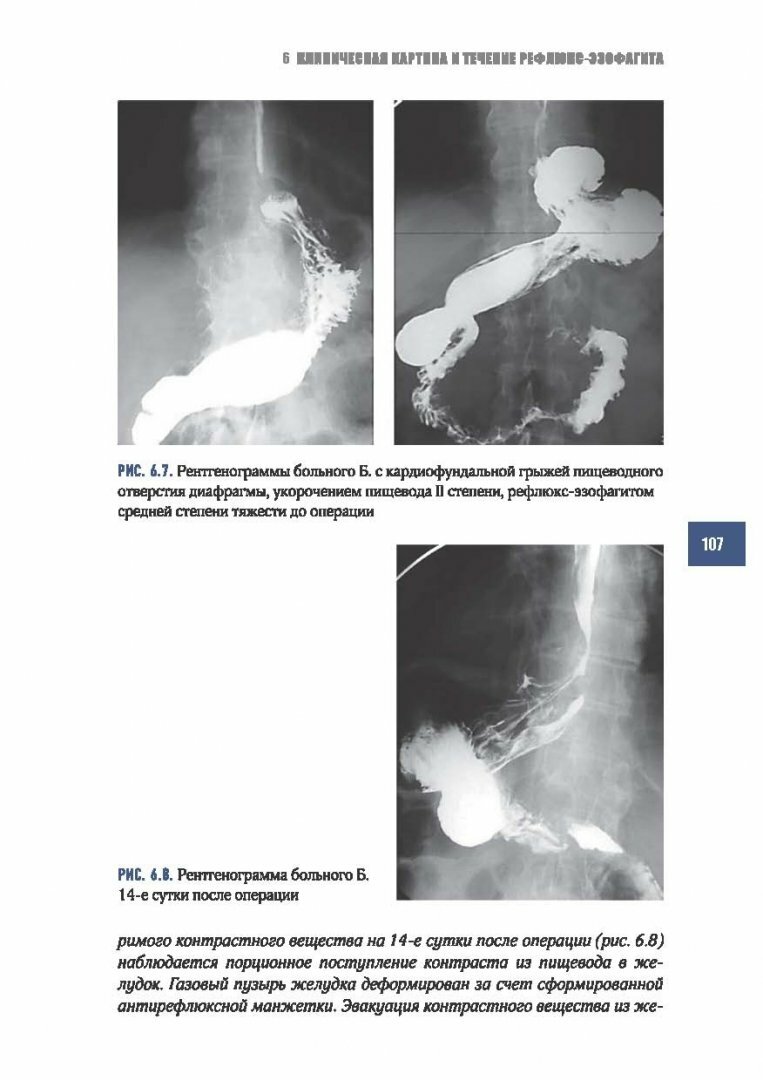

Книга: Рефлюкс-эзофагит (Черноусов Александр Федорович, Хоробрых Татьяна Витальевна, Ветшев Федор Петрович); Практическая медицина, 2017